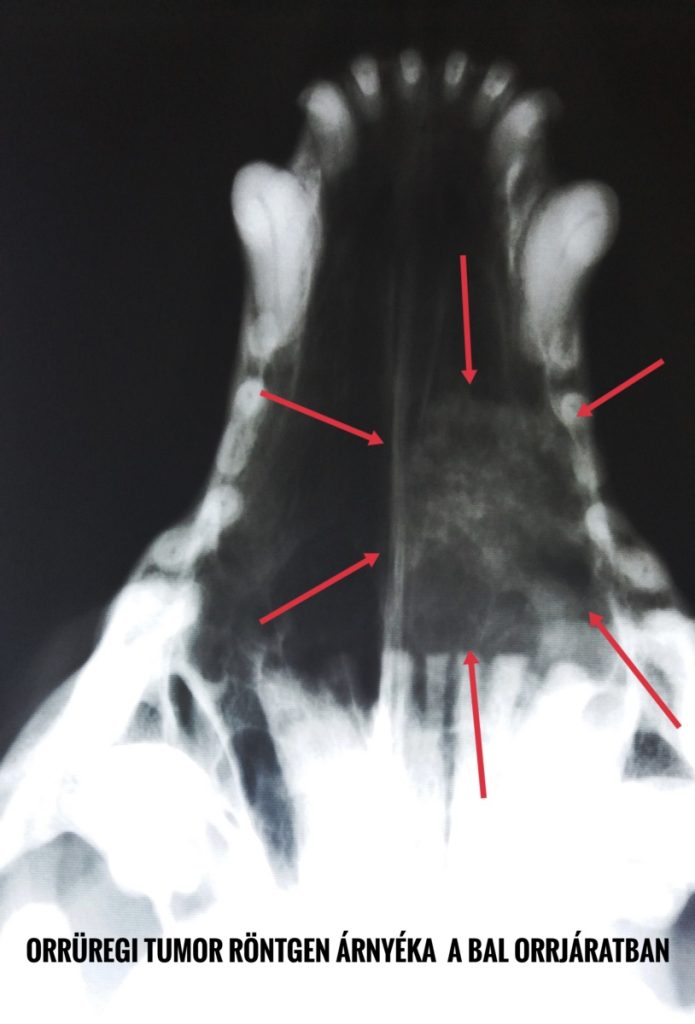

Orrüregi tumor RTG árnyéka

A kivizsgálás során:

- Vérvizsgálatot

- Orrüregi és mellkas röntgent

- Újabban három dimenziós képalkotó (CT vagy MRI) eljárásokat

- A környéki nyirokcsomók aspirációs citológiáját

- Orrüregi endoszkópos vizsgálatot (rhinoszkópia)

javasolhatunk, utóbbit mikrobiológiai és szövettani mintavétellel (biopszia) érdemes összekötni.